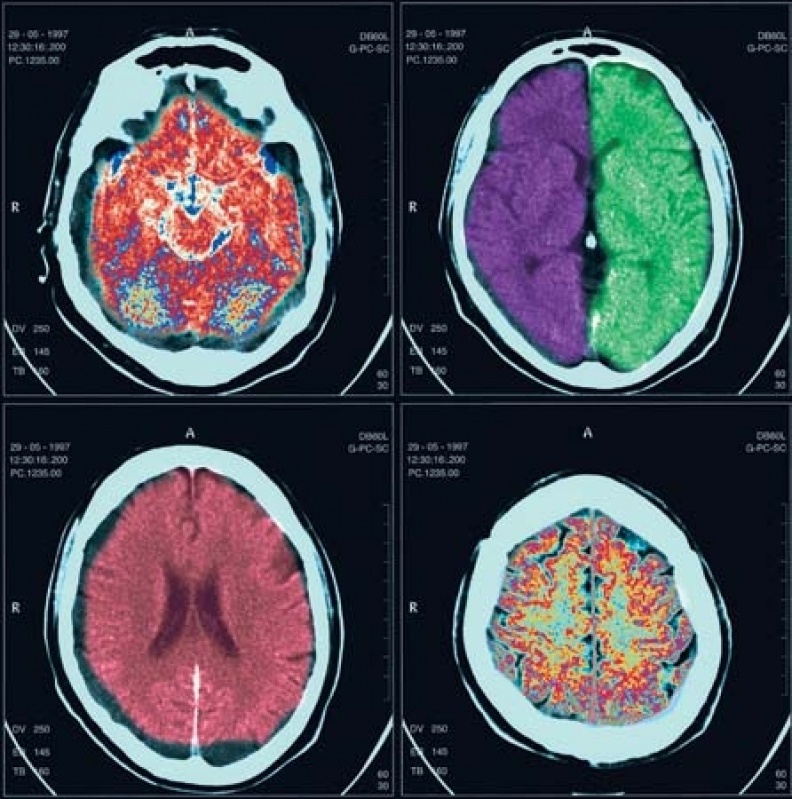

Medicom ExamesTomografia Computadorizada permite o médico iniciar um tratamento entendendo da real doença ou localização precisa da fratura de seu paciente, uma... Cotar Agora Saiba Mais

Medicom ExamesExames de tomografia torna possível ao médico começar um tratamento entendendo a real doença ou localização exata da fratura de seu paciente, já... Cotar Agora Saiba Mais

Medicom ExamesExame de tomografia computadorizada em São Paulo permite aos pacientes diagnosticar diferentes tipos de doença, podendo logo receber o tratamento... Cotar Agora Saiba Mais

Medicom ExamesExame de tomografia computadorizada permite visualizar órgãos e ossos dos pacientes em alta definição, isso possibilita entender o real... Cotar Agora Saiba Mais